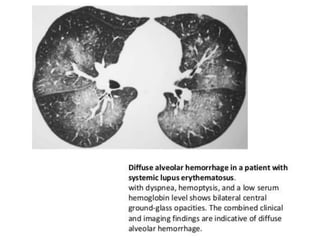

• Diffuse alveolar hemorrhage (DAH) and ALP are

characterized by acute onset of dyspnea with

• A sudden decrease in hemoglobin is highly

suggestive of DAH. Approximately one-half of

patients with DAH require mechanical ventilation

• Both ALP and DAH present with diffuse, bilateral

ground glass opacities on HRCT

• DAH and ALP carry a mortality rate of 50%